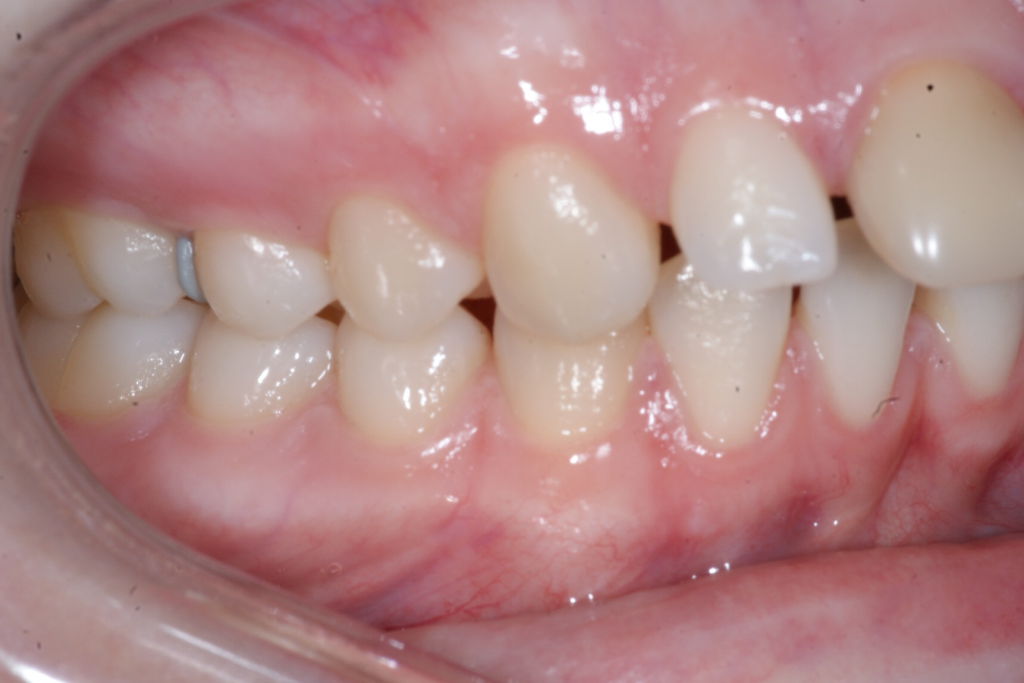

Correction d’une malocclusion de type Classe II division 1 avec excès d’espace aux 2 arcades.  Des appareils fixes (boîtiers) et une expansion palatine furent nécessaires pour améliorer ce sourire.  Traitement chez une adolescente, réalisé en 26 mois.